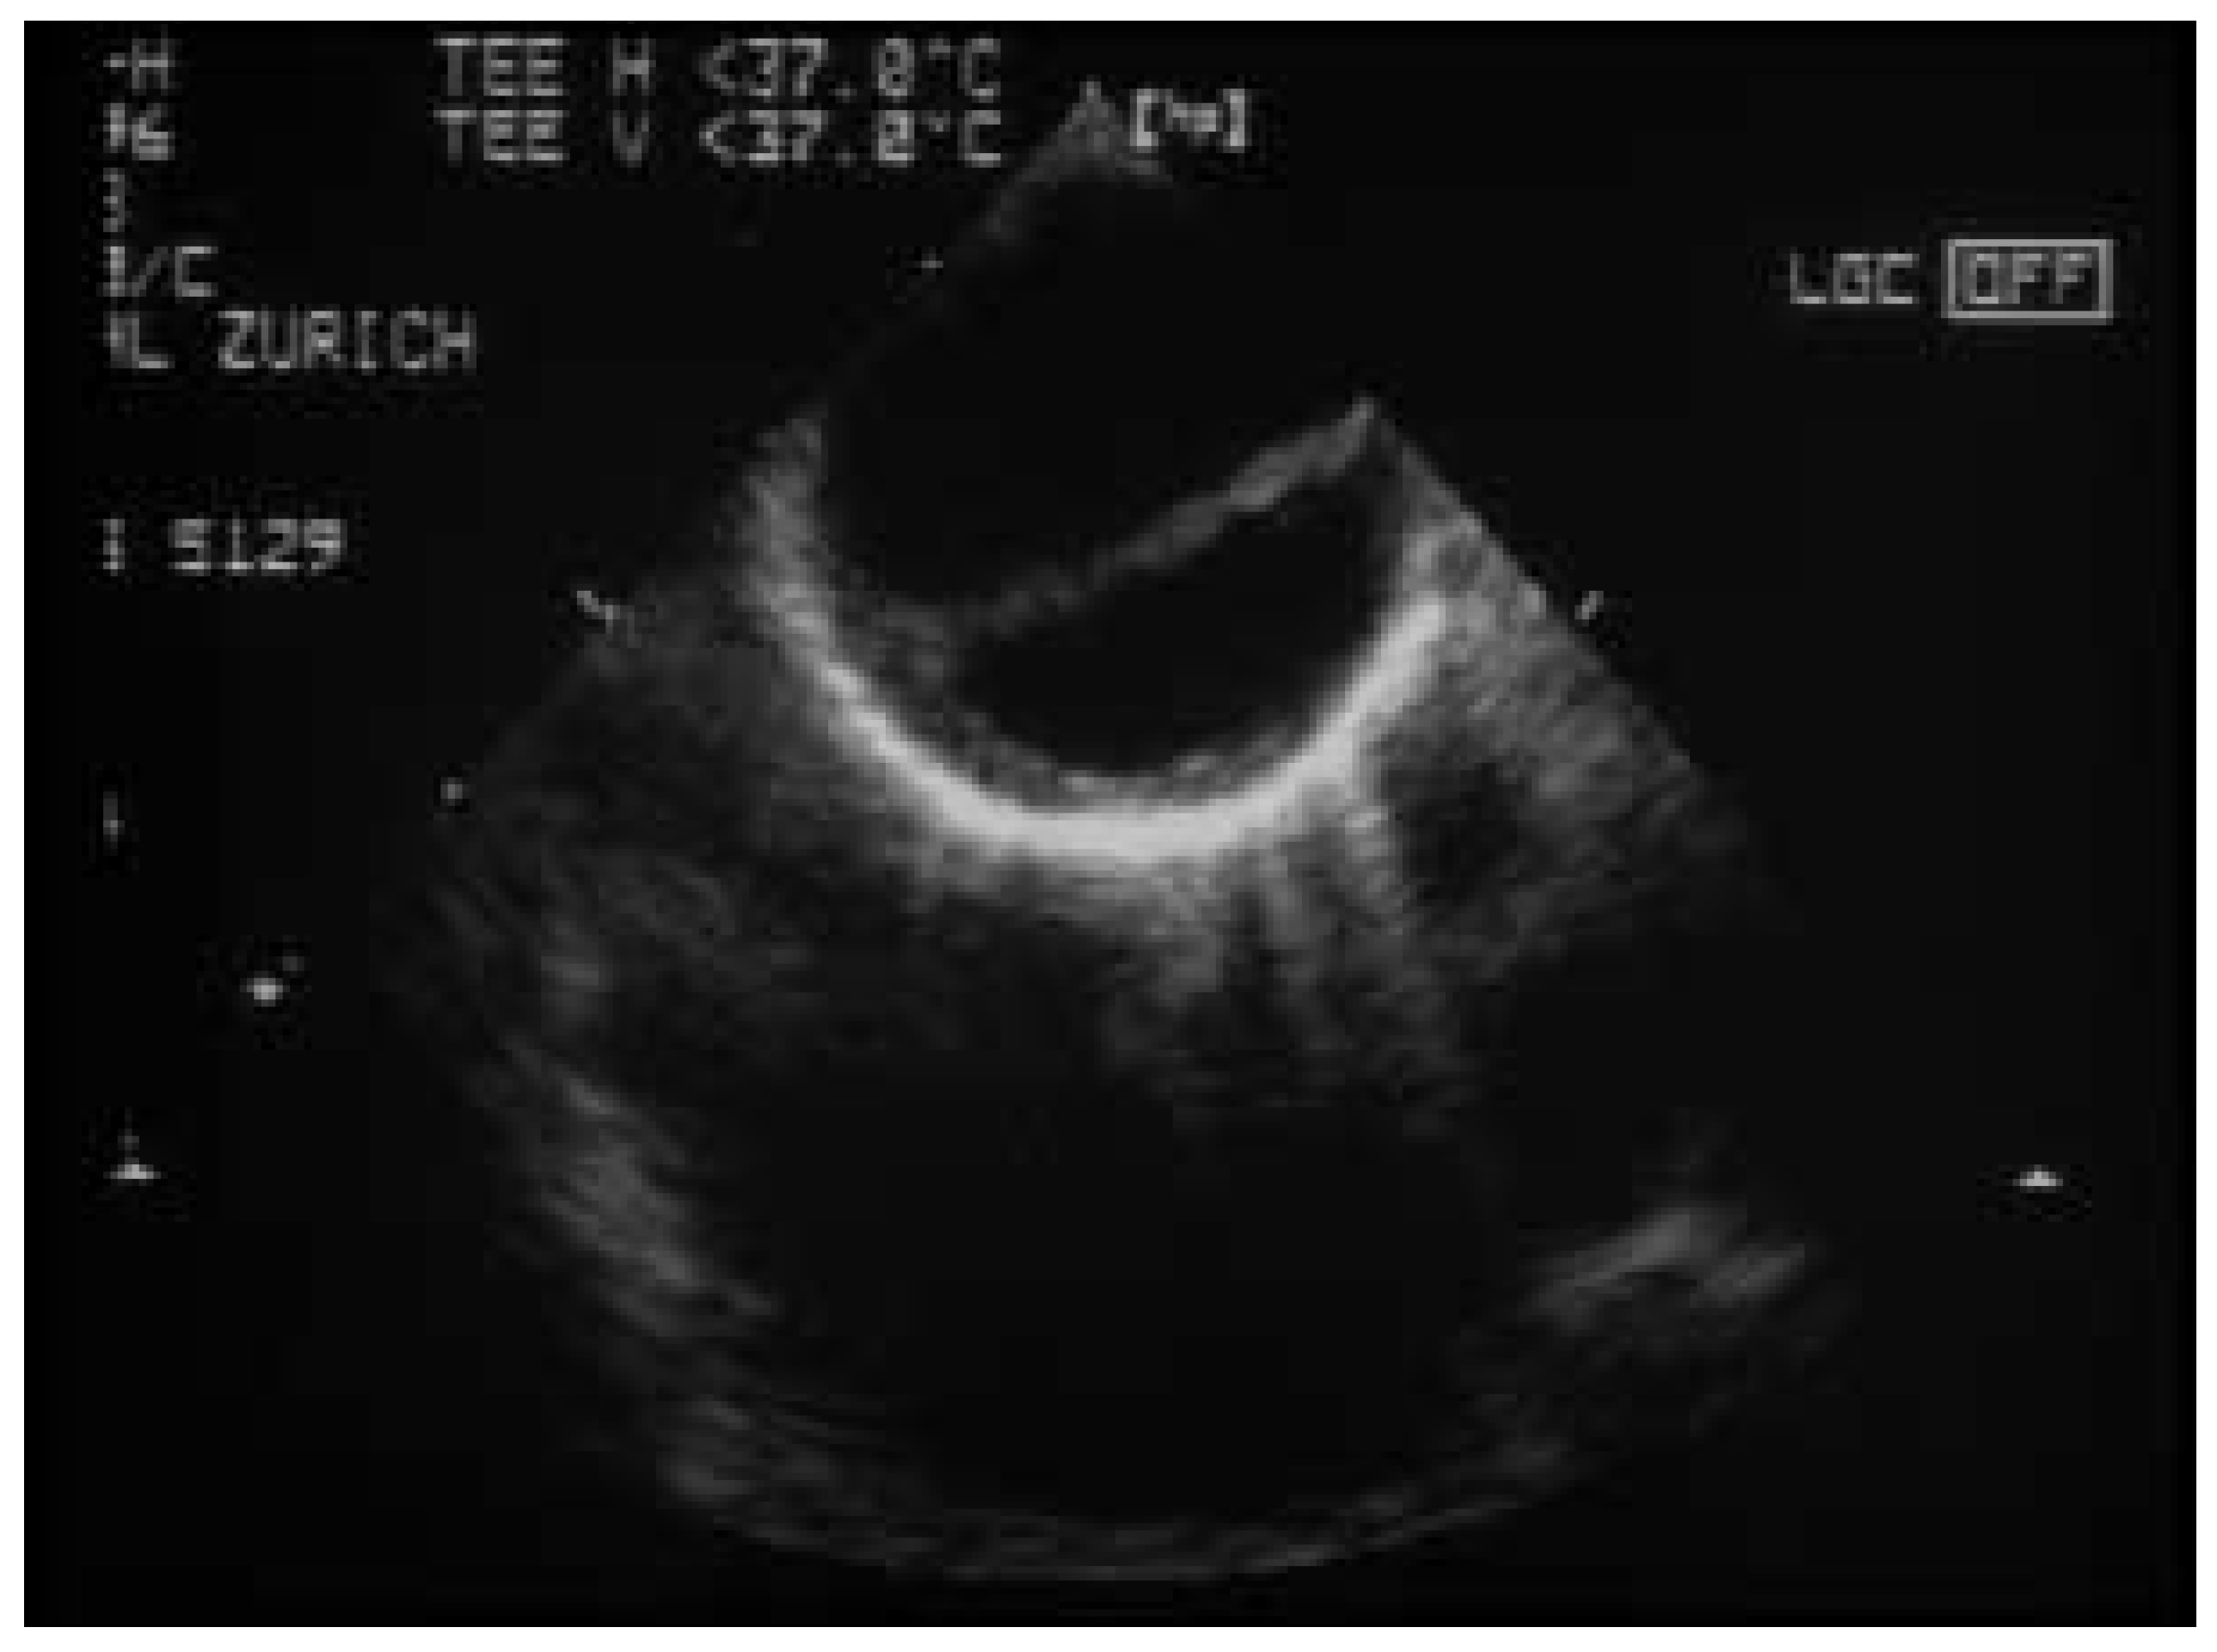

Figure 1.

Dissektion der thorakalen Aorta. Darstellung der Dissektionsmembran in der transösophagealen Echokardiographie.